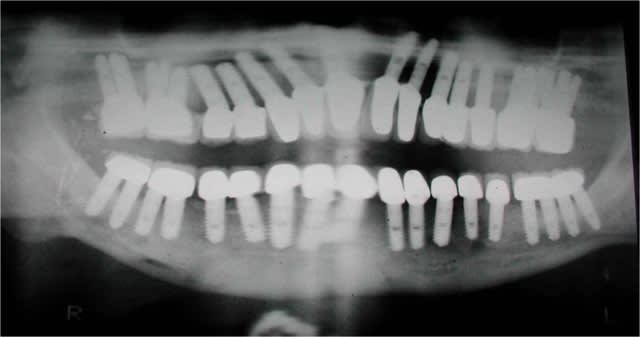

C’est ton humble avis, un verre peut être à moitié vide ou à moitié plein, les outils fournis par positdental ont permis de réaliser le plan de traitement implantaire, faire une MICIPE bi-maxillaire en 1 seule intervention n’est pas courant.

Il est inutile de faire le test de Sheffield pour s’assurer de la passivité de l’armature avec ce protocole, certain font des extansions postérieures d’autre non. Les implants distaux sont en 5.